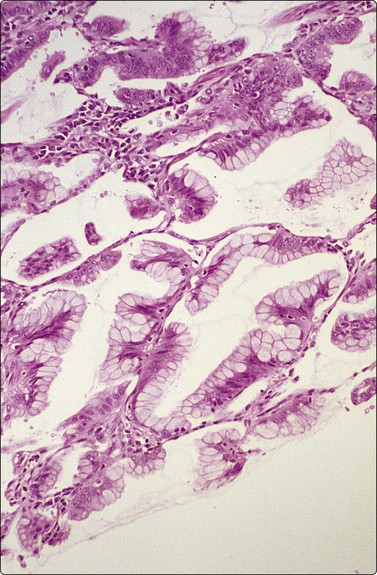

Fig. 8.20 Well-differentiated adenocarcinoma

Lepidic growth pattern. Tissue section (H&E, MP).

The cellular morphology of adenocarcinoma is similar to that described in brush material. Rosettes, acinar formations or cohesive cell clusters (Figs 8.18 and 8.19) represent anatomical structures removed from the tumor by the needle. The larger the gland formations, the less likely they are to be removed intact and, when only partly removed, deposit on the slide as flat sheets in a monolayer (Fig. 8.18): a useful indicator of glandular differentiation. Artifactual spaces are often seen in large tissue fragments and may be misinterpreted as acinar structures; however, where the spaces have an ‘anatomical’ rigidity, they may indicate glandular differentiation. Mucin secretion is difficult to identify without the aid of special stains, and vacuolation of the cytoplasm may occur as a result of degeneration or the presence of glycogen. In H&E- or Pap-stained material vacuoles with a central, inspissated, eosinophilic or orangiophilic center are very suggestive of mucin secretion and correspond to the intracellular lumina described ultrastructurally in adenocarcinomas. With MGG staining, mucin may be visible as magenta or purple material within the cytoplasm, either homogeneously or as red granules within a pale vacuole. Well-formed columnar cells or groups of palisaded cells may be a guide to glandular differentiation and terminal plates/bars may also be present. In the 2004 WHO classification,217 the definition of BAC was limited to a non-invasive process and is now an uncommon diagnosis, requiring full histological assessment; there is currently debate as to whether the term should be used at all, especially since a diagnosis of BAC cannot be rendered on small biopsy samples or cytological samples. However, it is still possible to suggest that a tumor may have a BAC-like component based on cytological features. These include large, cohesive, monolayered sheets which reflect the growth of neoplastic cells in a monolayer along alveolar walls, papillary processes, cell balls and clusters, intranuclear cytoplasmic inclusions and psammoma bodies (Figs 8.18-8.22). The radiogical appearance of a purely ground-glass opacity without a solid component is also suggestive of a BAC.